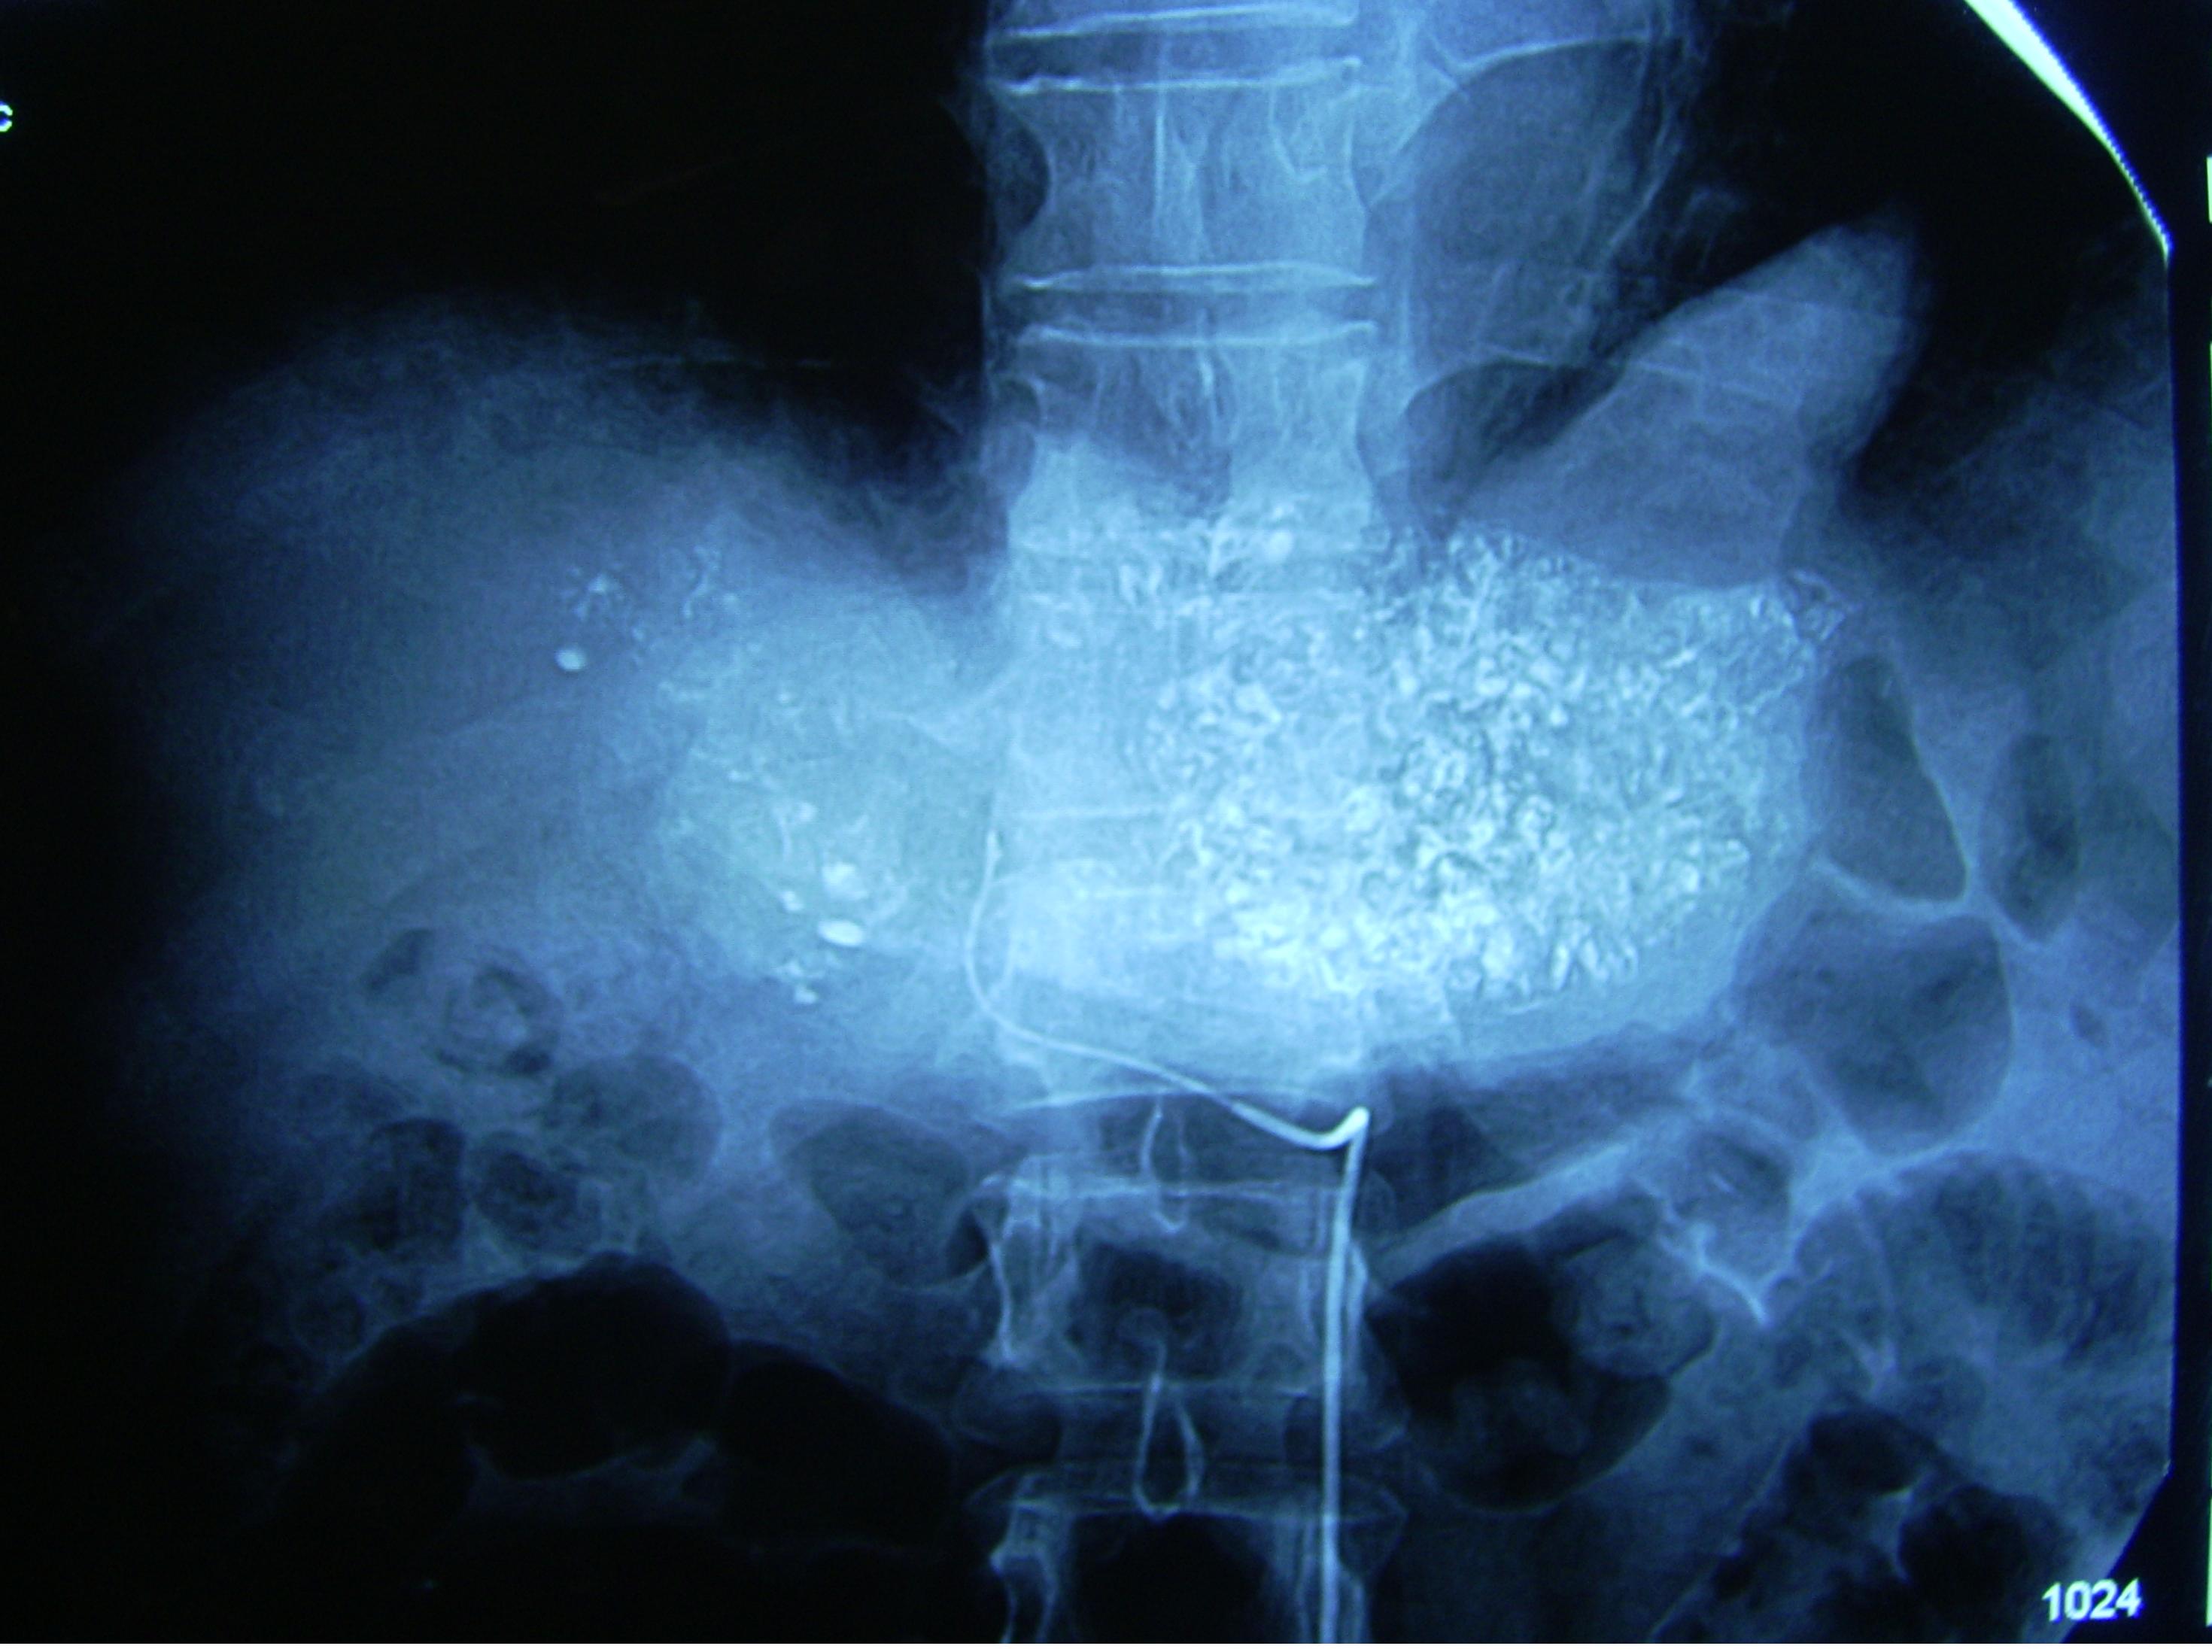

治疗过程:确诊后第2天进行经导管动脉化学栓塞治疗,也叫微创介入治疗。化学药物配伍方案为氟尿嘧啶脱氧核苷和羟基喜树碱,栓塞材料为无水乙醇和碘化油混悬液。治疗后2小时有恶心,无呕吐,肝区胀痛,给予颅痛定120毫克肌肉注射,15分钟后入睡。第2天早晨6点体温38.2摄氏度,采用物理降温,20小时后温度恢复正常。治疗后第4天出院,回家口服芦笋精胶囊,每天3次每次2粒,谷胱甘肽每天3次每次400毫克。1月后复查,肝内肿瘤范围明显减小,肿瘤组织里面由明显碘化油沉积。患者行动自如,KPS评分100分。3月后复查肿瘤范围进一步减小,按照原方案做了第2次微创介入治疗,以巩固疗效。患者酷爱吃火锅,虽然医生反复告诫其危险性,半年后的一天,患者独自一人去吃了一次,几小时后突然发生上消化道大出血,呕吐鲜血和血凝块1000多毫升,很快发生休克和昏迷,急诊抢救无效而死亡。

医生感悟:患者在经过两次介入治疗后,影像学复查肿瘤范围缩小,生活完全自理,没有疼痛症状,说明所选择治疗方案与纯粹姑息治疗比较有明显优势。患者发病时是医科大学2年级学生,来自某边远县城,出生时家庭经济条件较差,幼小的心灵受到一定压抑。后来抱养给经济条件很好,还开办了几家饮料厂的姨妈,从此受到宠爱和娇惯,养尊处优。刚刚考上大学,姨妈就给她买了一辆“宝马530”,一套3室1厅的住房。如果是在现在,一定会有众多的追求者。可是在那个年代,人们看问题的角度与现在有很大的差别。她是A型性格,待人接物很认真,又非常在意同学们每每投来的鄙夷的目光,越发感到孤僻,冷凄凄的一个人,不与同学们来往。她姓杨,有同学偶尔背后称她“洋美女”,联想到自己来自偏远地区,反而理解成“土丑女”,心理更加压抑。于是每天晚餐都去火锅店找刺激,天天吃,月月吃,整整吃了一年。当年的饮食卫生监管很松,火锅底料大都是反复使用,甚至有号称“百年老料”的火锅店。这样的汤料,难免含有较多的致癌物质,例如苯并芘、亚硝酸盐等。还有些商家,为了引诱吃客,使出一些更为猛烈的手段,比如在汤料中加入头痛粉、*粟罂**壳等,造成满街飘香,但有促进炎症、抑制免疫的害处。一些食材比如牛毛肚,使用的防腐剂福尔马林,已在1995年被世界卫生组织列为“可疑致癌物质”,到2004年被认定为“1类致癌物质”。压抑的心情又导致免疫力低下,容易患多种疾病。患者在入学时要经过反复体检,因此,正是上述诸多因素致使她在不长的时间里发展为晚期肝癌,因为我国典型的乙型肝炎、肝硬化、原发性肝细胞癌3部曲,需要20年左右甚至更长的时间才能完成。然而,患者最终的死亡原因,不是癌症本身,而是肝硬化、门静脉高压导致的食管胃底曲张静脉破裂出血后循环衰竭。降低门静脉高压最可靠的方法,也是一种介入治疗技术,叫做“经颈静脉肝内门腔静脉支架分流”,自1995年以来就已经在开展。但是,这个操作要在肝内经过肝静脉穿刺门静脉,而该患者是弥漫型肝癌,属于反指征,如果是结节型或者巨块型,还可以考虑。而肝胆外科医生也不推荐“门静脉奇静脉断流”手术治疗。因此,只能采取调节生活方式来预防出血。